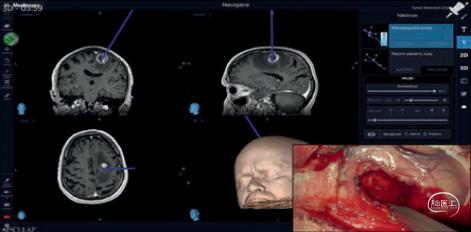

根据患者术前的影像资料,如CT、MR、CTA、MRA、fMRI、PET、SPECT等图像,通过美敦力S8导航的高级计划系统,可以实现自动三维重建工具创建肿瘤、白质纤维束、脑组织表面和脑血管模型;通过3D模型的自动化调整可以允许医生快速可视化解剖结构,并通过多种注册方式实现大脑的多模虚拟与现实融合,通过虚拟颅骨切口和虚拟内窥镜提供具象化并计划手术入路,以制定手术方案。

在术中我们也能通过O-arm提供实时的影像信息,帮助临床医生确认手术效果及监测颅内是否出现出血等手术并发症;此外美敦力的术中神经电生理监护设备,可以针对全麻状态下的病人进行神经功能进行评估和监测,对整台手术起到保驾护航的作用,避免病人术中神经损伤,临床意义非常重大。

根据患者数据模拟结构解剖图,能够清楚展现各个部位并解决视角盲区,同时可将整个手术过程在术前模拟进行,减少手术时间、并发症的发生率和辐射暴露。